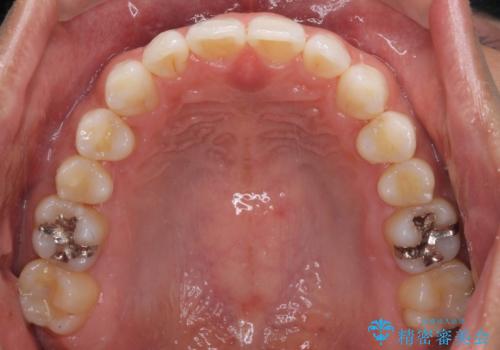

- 上下前歯のデコボコを気にして来院された患者様です。

以前矯正をした後戻りということで、歯列不正はそれほど大きくなかったため、インビザライン・ライトを用いて矯正治療を行うこととしました。

1日22時間以上しっかりと装着してくださったので、半年かからずに治療を終えることができました。